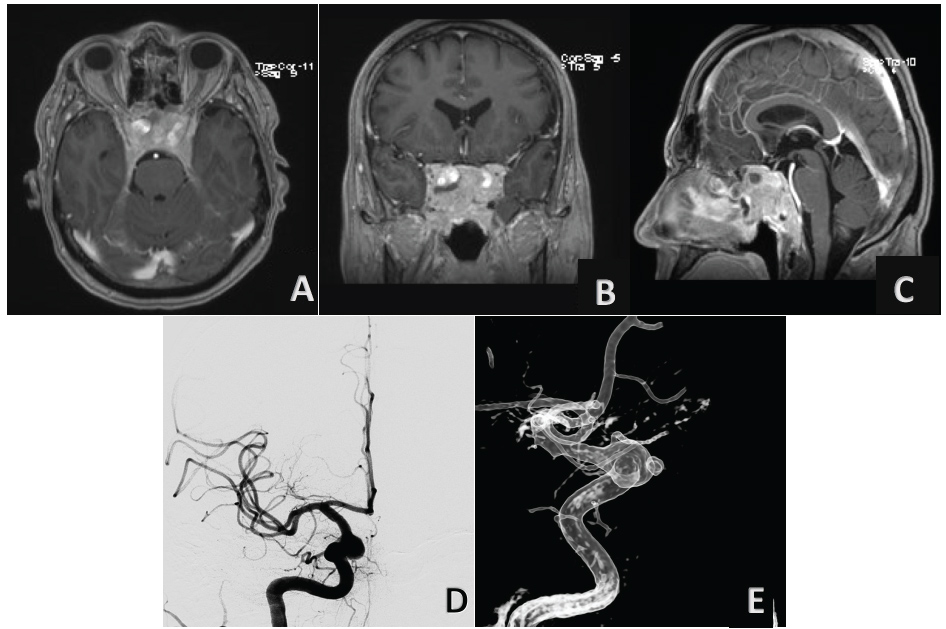

Non-contrast head CT revealed a large destructive central skull base mass with hyperdensity in his context. A further examination with pre-and post-gadolinium brain MRI, underlined the limits of the skull base mass centred in cellar region with erosion of sphenoid sinus and clivus. It was extended inferiorly to the magnum foramen and occipital condyles, laterally to the petrous apices, sigmoid sinus and jugular bulbs; superiorly occupying the chiasmatic cistern, encasing optic nerves and both internal carotid arteries (Figure 1). A large flow void, within the region of the right carotid siphon has been shown (Figure 2). Digital subtraction angiography (DSA) was performed that confirmed a pseudo-aneurysm of cavernous segment of right ICA with a bleb on the anterior side (Figure 1).

Figure 1: Contrast-enhanced T1-weighted magnetic resonance images in the axial A) Coronal; B) And sagittal planes; C) Demonstrate an intra and parasellar tumor; Four-vessels angiogram in anteroposterior; D) And three-dimensional lateral view; E) Reveals a large pseudo-aneurysm of cavernous segment of right ICA with bleb on anterior side. View Figure 1